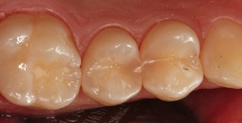

Fall 6 Minimalinvasive Behandlung von tiefen Approximalläsionen an Zähnen 14 und 15

Bei dem 26-jährigen, frisch approbierten Zahnarzt imponierte eine untypisch hohe Kariesaktivität mit etlichen, teils sehr tiefen Approximalläsionen, die einer therapeutisch- restaurativen Intervention bedurften. An den Zähnen 14 und 15 zeigte sich eine auffällige Transluzenzänderung des Zahnschmelzes, was immer ein untrügerisches Zeichen für eine darunterliegende, bereits in das Dentin penetrierte Karies darstellt (Abb. 23). Die Abbildung 24 verdeutlicht – noch während der Exkavation – das Ausmaß des vorgefundenen Defektes. In der Abbildung 25 sind die vollständigen Kavitäten, bereits mit Teilmatrizen und einem Palodent V3-Spannring isoliert, erkennbar. Durch den hervorragenden Separationsdruck dieser Art von Spannringen können benachbarte Approximalläsionen in der Regel problemlos zeitgleich versorgt Anwerden. Nach der adhäsiven Vorbehandlung – im vorliegenden Fall mit einem klassischen Mehrflaschen-Etch&Rinse- Adhäsiv (Abb. 26) – erfolgte die Versorgung mit SDR flow+ in der Farbe A3 in zwei horizontalen Inkrementen. Beide Inkremente, die eine Dicke von ca. 3 mm aufwiesen, wurden für je 40 Sekunden gemäß Herstellerangaben polymerisiert. Eine gemeinsame abschließende Polymerisation für 20 Sekunden nach Entfernen der Matrizen ergänzte das Aushärtungsprotokoll. Die Abbildung 27 zeigt die Situation direkt nach Ausarbeitung und Politur, die Abbildung 28 bei einer weiteren Nachkontrolle nach drei Monaten. Es zeigte sich nach der Rehydrierung der Strukturen eine deutlich bessere Farbadaptation als initial, unmittelbar nach dem Legen.